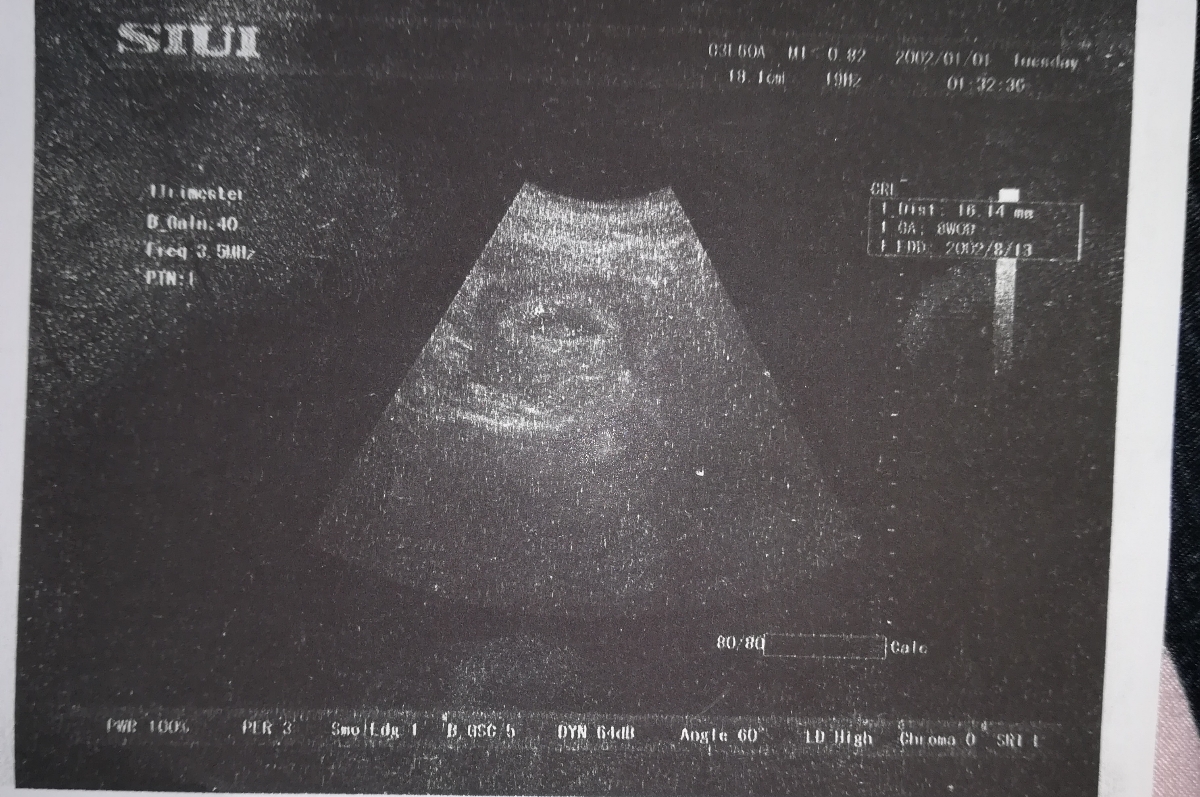

این عکس بچم😘😘

اون قسمت بالا ک ×داره فیبروم

میگم تو اوما زده اندازه جنین تو این هفته 3 سانت. ولی برا من 29 م م. کوچیک نیس؟

فک کنم اون ک نوشته 16.14